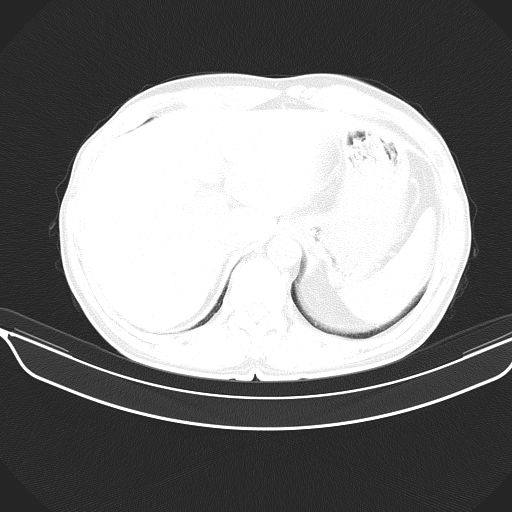

以下是引用shuiyuan在2010-3-1 10:45:00的发言:[br]考虑左肺上叶中心型肺癌伴阻塞型炎症,邻近胸膜受侵。

以下是引用心路寻觅在2010-3-1 10:23:00的发言:[br]1、考虑左肺上叶周围型肺癌[br]2、右上肺陈旧性病灶。[br][br][本贴已被 心路寻觅 于 2010-3-1 10:40:18 修改过]